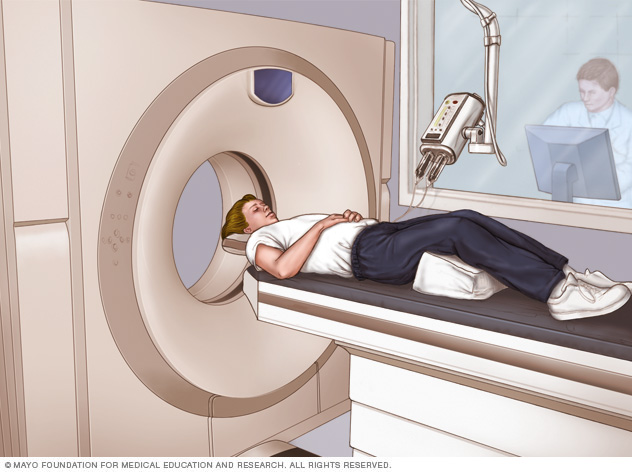

In addition, new minimally invasive surgical techniques, such as MRI-guided laser ablation, show promise at reducing seizures with fewer risks than traditional open brain surgery for epilepsy.

Researchers are also studying stereotactic radiosurgery as a potential treatment for some types of epilepsy. In this procedure, doctors direct radiation at the specific area of your brain that is causing your seizure.